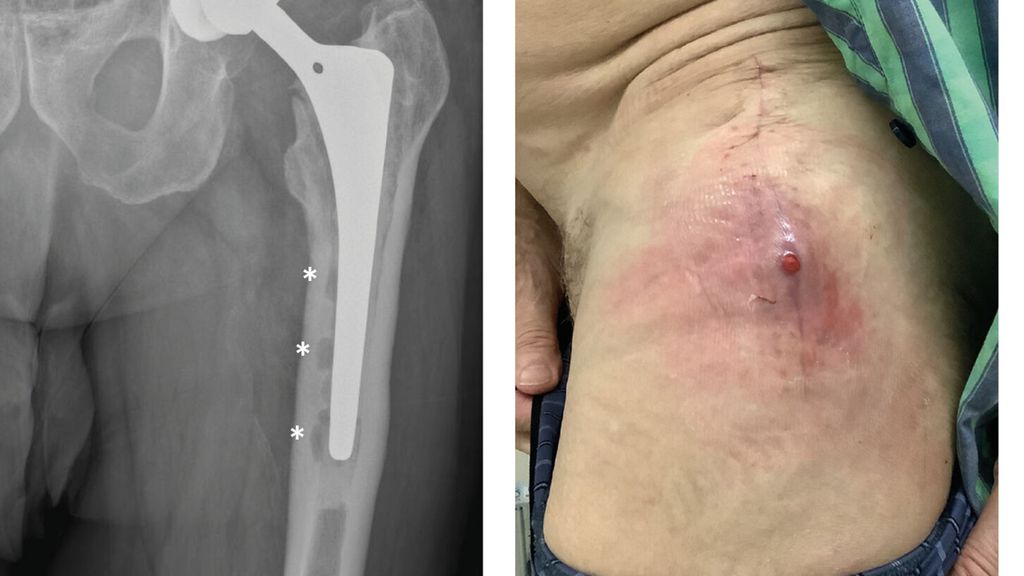

Abb. 1: Patient mit chronischer Hüftendoprotheseninfektion. Radiologisch zeigen sich infektionsbedingte periprothetische Osteolysen (*, a) und klinisch imponiert eine kutane Fistel (b).

Anhand der klinischen Zeichen und der Symptomdauer unterscheidet man zwischen akuter und chronischer PPI. Die akute PPI ist durch eine kurze Symptomdauer (<3 Wochen) charakterisiert. Sie tritt entweder in der frühen (<4 Wochen) Phase nach endoprothetischem Gelenkersatz (akute postoperative PPI) oder aber verzögert (>4 Wochen, ggf. erst mehrere Jahre) nach Endoprothesenimplantation im Rahmen einer hämatogenen Streuung eines endoprothesenfernen Infektionsherdes (akute hämatogene PPI) auf. Typischerweise imponieren hier lokale Infektionszeichen wie Schmerzen, Schwellung, Rötung, Überwärmung oder eine prolongierte Wundsekretion (>7 Tage). Die Unterscheidung zwischen akuter und chronischer PPI basiert auf den Eigenschaften des bakteriellen Biofilms. Beim Vorliegen einer akuten PPI ist von einem unreifen bakteriellen Biofilm auf der Endoprothesenoberfläche auszugehen. Bei der chronischen PPI (>4 Wochen postoperativ) mit längerer Symptomdauer (>3 Wochen) liegt hingegen ein potenziell reifer Biofilm vor. Die klinischen Symptome sind in der Regel weniger ausgeprägt. Jedoch kann das Vorliegen einer kutanen Fistel oder von radiologischen Zeichen der Endoprothesenlockerung auf eine chronische Infektion hinweisen (z. B. Abb. 1).